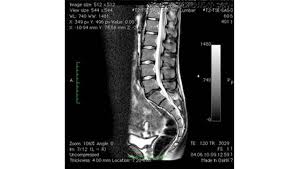

Bandscheiben op lws 4 5. Sie kommen meist zwischen den Wirbeln LWK Lendenwirbelkörper 45 und LWK 5SWK 1 Sakralwirbelkörper vor an der vorletzten und letzten Bandscheibe. Bandscheibenvorfälle sind Teil einer natürlichen Abnützung des Gewebes. Drückt der Gallertkern auf einen Rückenmarksnerven leiden Betroffene unter starken Rückenschmerzen die teilweise bis in Arme und Beine ausstrahlen.

Ursachen Diagnose und Therapie. Wie der Bandscheiben-Vorfall Prolaps ist die Bandscheiben-Vorwölbung Protrusion besonders häufig in der Etage bei L4L5 zwischen dem 4.

Wenn die Physiotherapie und Medikamente nicht mehr helfen und die Schmerzen zu stark sind oder wenn der Druck auf die Nerven Ausfälle verursacht Taubheit Muskelschwäche Lähmung sollte eine Operation in Betracht gezogen werden. Bandscheibenvorfall LWS Übungen - Hier findest du 5 effektive Übungen bei einem Bandscheibenvorfall in der Lendenwirbelsäule inkl. Es geht mir zur Zeit nicht gut mache mir auch große Sorgen wie es wird in den nächsten Tagen und Wochen mit den Schmerzen und Beschwerden. Ich wurde am 4. Frank aus München in. Probieren Sie es selbst aus. Sie kommen meist zwischen den Wirbeln LWK Lendenwirbelkörper 45 und LWK 5SWK 1 Sakralwirbelkörper vor an der vorletzten und letzten Bandscheibe. Die Bandscheiben der Wirbelsäule übt eine Art Stossdämpferfunktion aus und dient der Elastizität und der Beweglichkeit der Wirbelsäule. Lendenwirbel und dem 5.

Die Bandscheibenvorfälle an der Lendenwirbelsäule sind die häufigsten Bandscheibenvorfälle an der Wirbelsäule. In der Regel verschwinden die Schmerzen zwar nach der OP es kann aber immer sein dass sich Symptome nicht zurückbilden. Wenn die Physiotherapie und Medikamente nicht mehr helfen und die Schmerzen zu stark sind oder wenn der Druck auf die Nerven Ausfälle verursacht Taubheit Muskelschwäche Lähmung sollte eine Operation in Betracht gezogen werden. 3053 Beiträge ø047Tag Hallo vor 1 Woche hatte ich eine große Bandscheiben-OP. Wie der Bandscheiben-Vorfall Prolaps ist die Bandscheiben-Vorwölbung Protrusion besonders häufig in der Etage bei L4L5 zwischen dem 4. Bandscheibenvorfall 4-5 Lendenwirbel Hey S-A2011 danke für Deine Erzählung. Alleine in Deutschland werden jährlich ungefähr 150000 Bandscheibenvorfälle operativ behandelt.